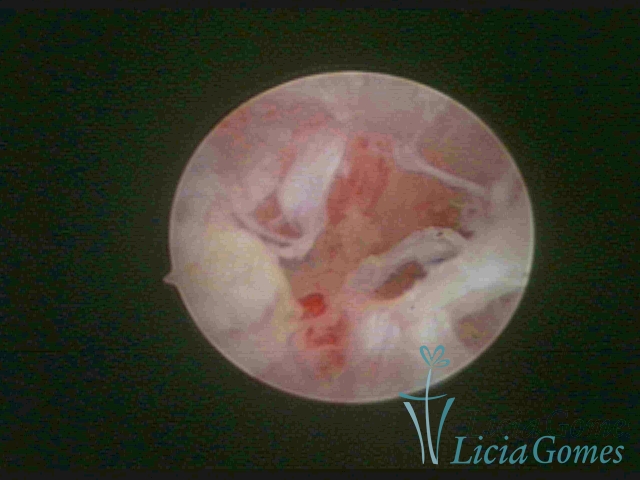

• SINÉQUIA TIPO FIBROSA